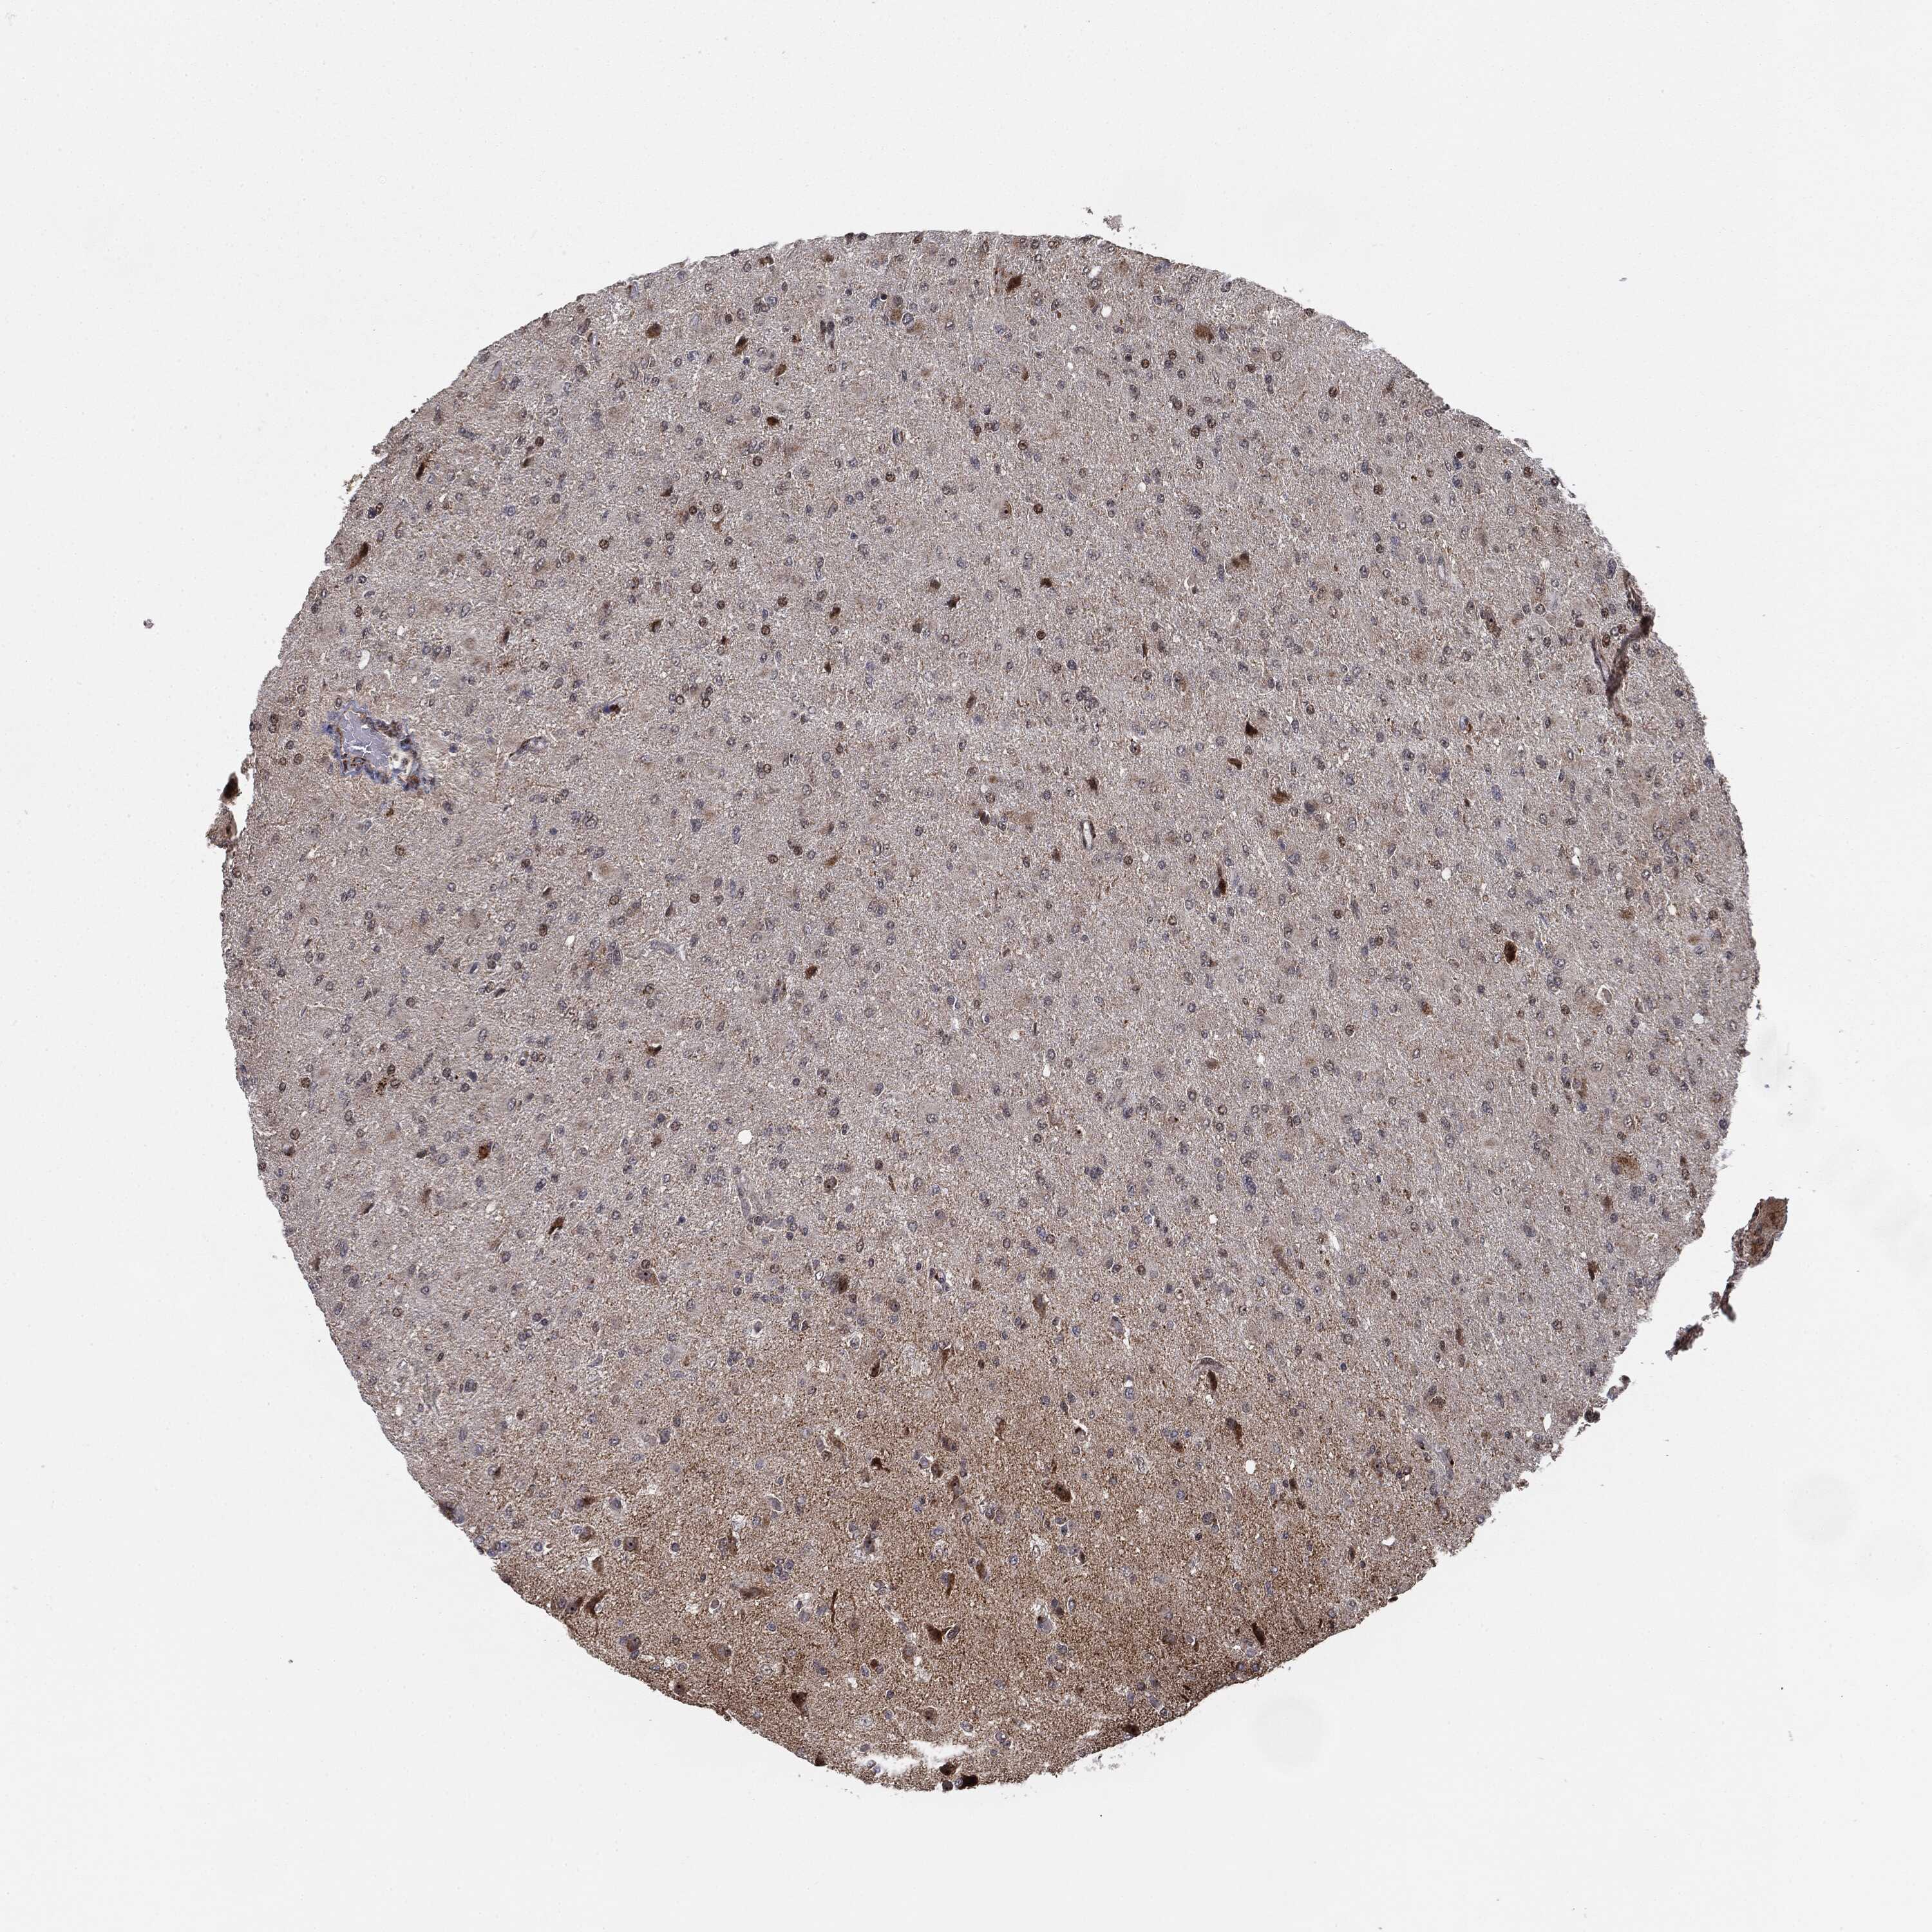

GLIOMA - Protein expressioni

A mouse-over function shows sample information and annotation data. Click on an image to view it in a full screen mode. Samples can be filtered based on level of antibody staining by selecting one or several of the following categories: high, medium, low and not detected. The assay and annotation is described here.

Note that samples used for immunohistochemistry by the Human Protein Atlas do not correspond to samples in the TCGA dataset.

Antibody stainingi

Antibody staining in the annotated cell types in the current human tissue is reported as not detected, low, medium, or high, based on conventional immunohistochemistry profiling in selected tissues. This score is based on the combination of the staining intensity and fraction of stained cells.

Each image is clickable and will lead to virtual microscopy that enables deeper exploration of all samples and also displays staining intensity scores, fraction scores and subcellular localization as well as patient and tissue information for each sample.

Antibody HPA031335

Antibody CAB004076

Antibody CAB080153

Antibody CAB080157

Glioma, malignant, Low grade

Glioma, malignant, High grade

Glioma, malignant, NOS